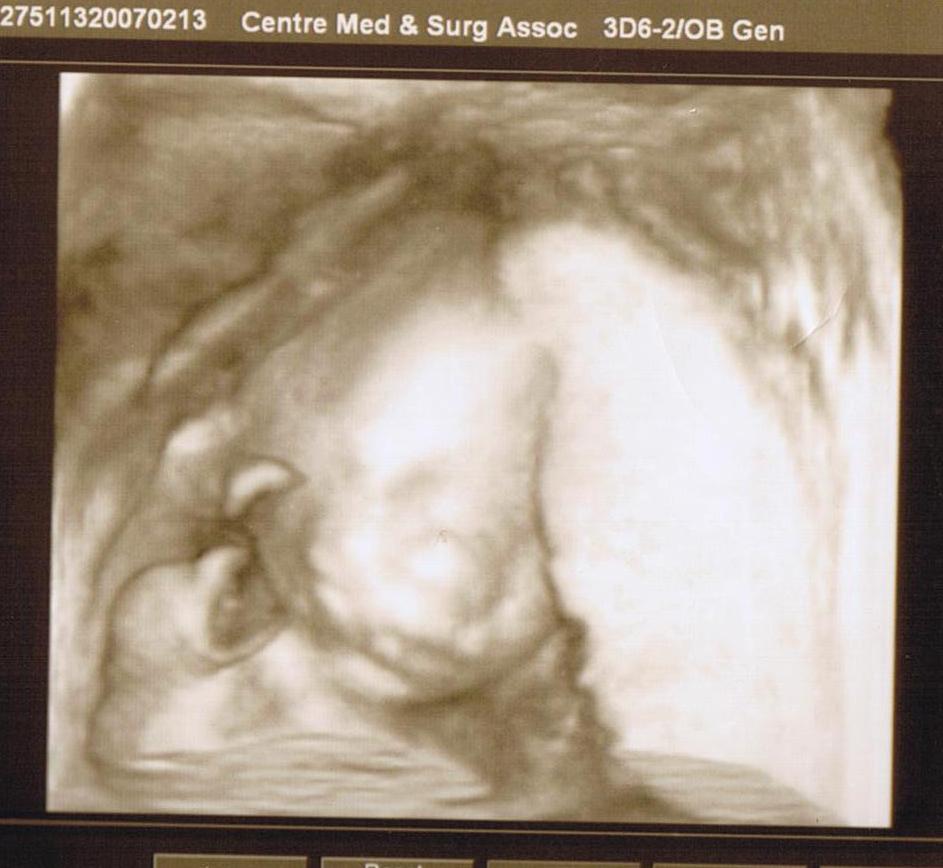

I am pregnant! You are going to become uncles or aunts la.

我懷孕9週多了. 預產期大約會在明年的6月或者是7月初吧. 其實也沒打算這麼早就跟大家說的, 因為我到現在還沒有去產檢. 我的保險要在12月才生效, 而我約好了在12月1日就去見姑娘做檢查, 6 日就可以見醫生看報告啦.

本來跟老公仲好期待星期五就可以同bb 見面囉. 因為香港 醫生是檢查一次就照一次架嘛. 點知, 听講美國的醫生是不會幫媽媽照超音波的, 他們是用手摸媽媽的肚, 覺得沒問題就唔照, 一直到18 ~ 19週先照一次看是男是女, 如果到時bb 不合作, 看不到的話, 就要出生先知性別囉. 好失望啊. 我好想看下阿b 是點樣架.